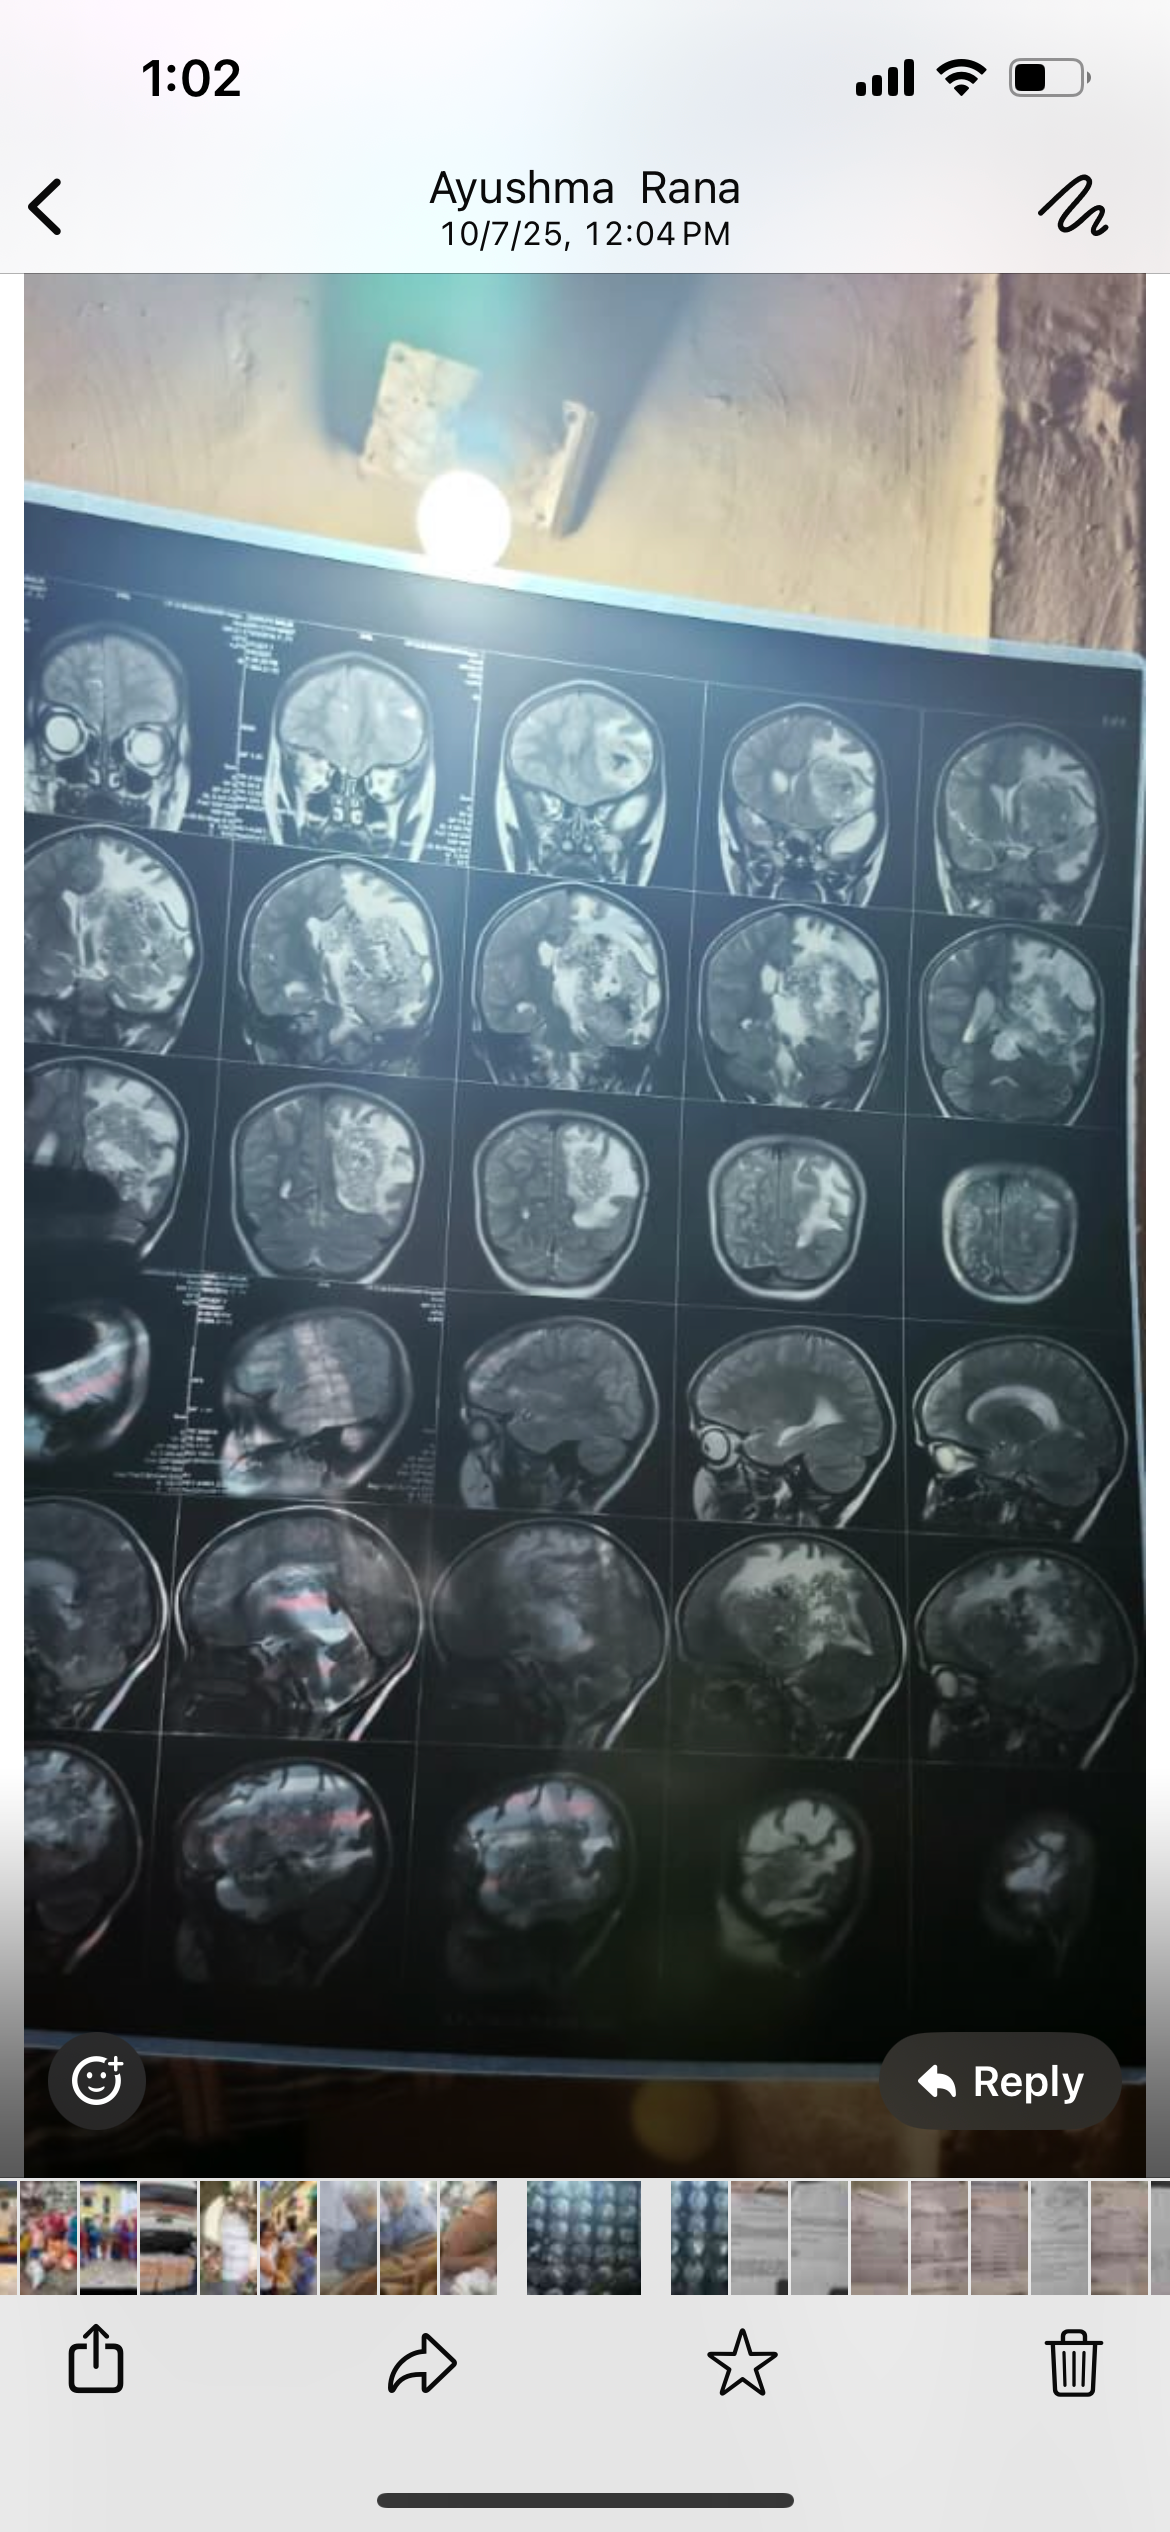

We are raising funds for 7 year old girl Shruti Malik, daughter of my friend’s employee. She is diagnosed with brain tumor and recently undergone operation to decrease the pressure in her brain. The doctors are waiting for her to gain strength so they can do surgery to remove her tumors.

The massive tumor is on the left side of her brain and is present on multiple lobes of the brain.